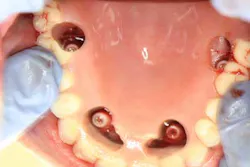

In the aforementioned case, our first step was to make a full upper denture. (2) Preop pictures, capturing the patient’s smile, high lip line, and resting line are recommended. A new lower partial denture is also fabricated since the existing lower partial “floated” and did not offer an ideal opposing arch to provide balanced occlusion against the AO4. The patient went to surgery, was edentulated (including removal of No. 10 implant), and had a total of four implants placed. He presented to my office immediately following surgery with the healing caps on.

We then took the full upper denture and with bite registration material, recorded where the implants were. We removed the acrylic in the denture and verified location, ensuring that we had a clear line of access to the implants; adjustments were made accordingly. The abutments were then placed intraorally and a rubber dam was situated so that the sutures were not disrupted.

Once the denture was situated in the mouth properly, acrylic was painted in the access sites to set the abutments in place within the denture. It was allowed to set (approximately three minutes) and then the entire denture was removed.

The palate was completely removed from the denture and the voids were filled in around the abutments. We did a rough try in to ensure vertical dimension and bite. The underside of the denture was filled in with acrylic to give it a convex shape so hygiene was ideal. The denture was seated and torqued to 15nCm. The access sites were packed with cord and then covered with resin. Since the patient was still numb, the bite was assessed the following day and adjusted accordingly. Total treatment time in my office was approximately 3.5 hours.

FINAL TEMPORARY AO4 PHOTOS